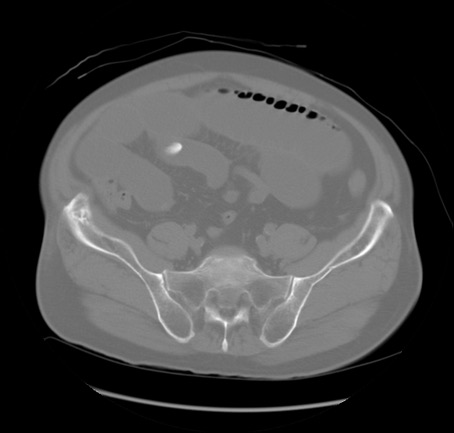

矢状断像

【症例】 60歳代男性

【主訴】 腹部膨満、嘔吐

【現病歴】5日前頃より倦怠感を認め食事量減少し4日前の朝嘔吐、食事摂取困難となった。 3日前近医受診し点滴施行され整腸剤などを処方された。 当日他院を受診し、腹部膨満著明、炎症反応の上昇(CRP10.8、WBC11200)あり、紹介受診となる。

【身体所見】 意識JCS1 受け答えがはっきりしないBP 111/57mHg、 P 67bpm、、BT35.2°C、SpO2 97%(RA)、 腹部:膨隆、打診で鼓音あり、全体的に圧痛有り、腸蠕動音(-)、反跳痛ははっきりせず。

【データ】WBC 11400、CRP 14.20